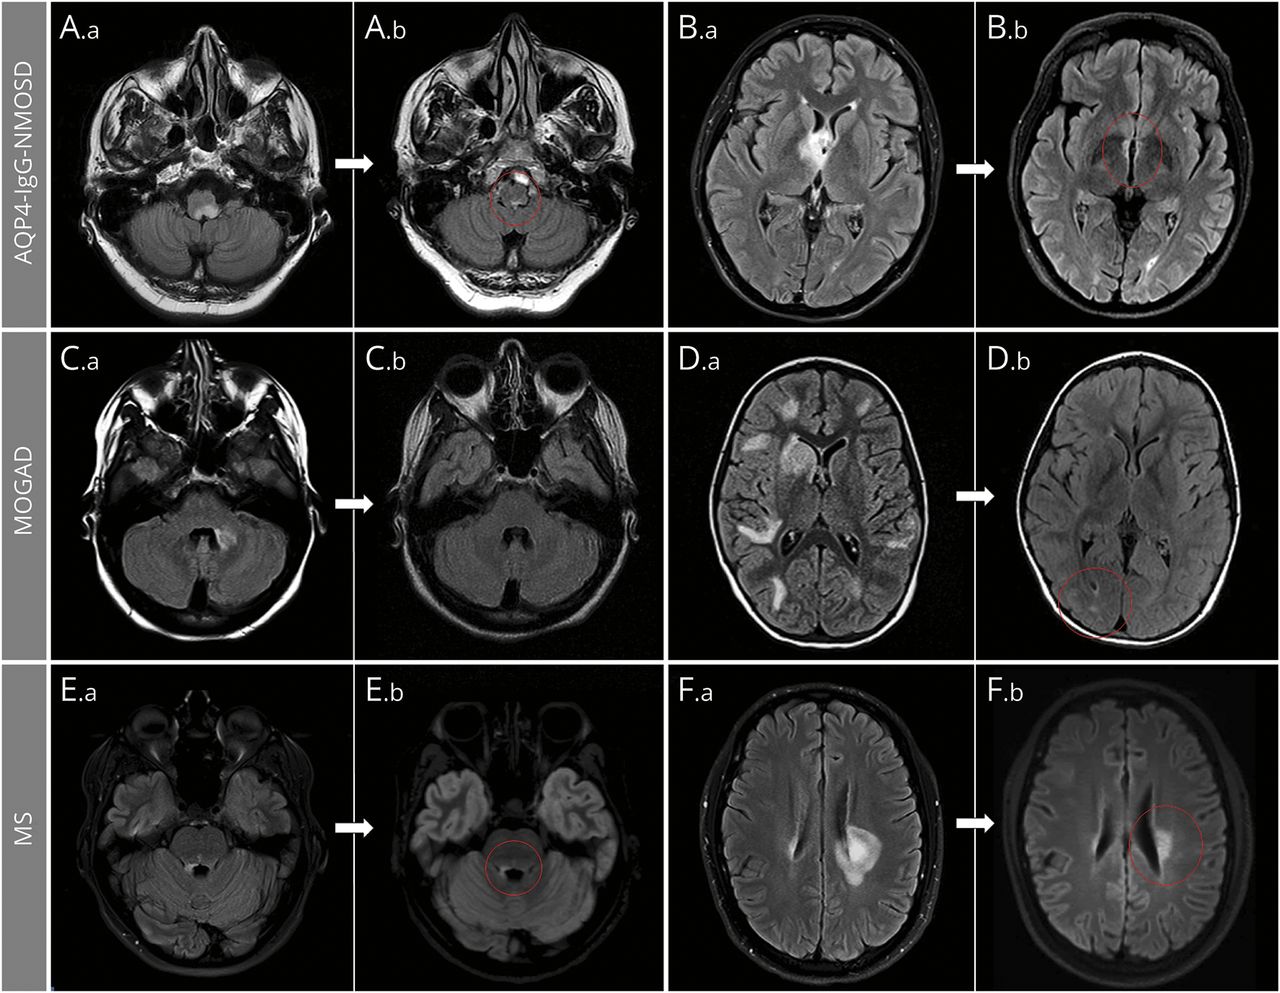

(A)条图显示了不同的频率分析措施的患者水通道蛋白4-immunoglobulin G-positive neuromyelitis视谱系障碍(AQP4-IgG-NMOSD)(深蓝色酒吧),髓少突细胞glycoprotein-immunoglobulin G-associated障碍(MOGAD)(浅蓝色酒吧)和多发性硬化症(MS)(绿酒吧)在大脑和脊髓。尽管规模最大的减少在AQP4-IgG-NMOSD和MOGAD病变有关,只有后者的MRI异常显示完整的决议后续在大多数情况下。相反,病灶显示的大小会减少最小的女士在随访,类似于AQP4-IgG-NMOSD病变,不太可能完全解决。两组统计学意义差异由星号表示的酒吧(* * *)。(B)中位数为大脑和脊髓损伤轴向最大的区域,并为脊髓矢状,敏锐,MRI随访3组。确切的p所示值不同的比较表2和3。